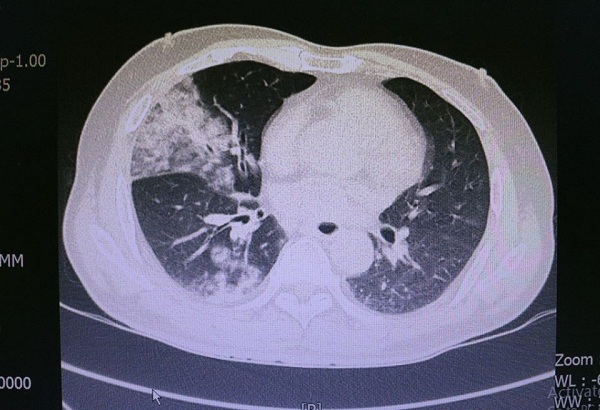

Tình trạng viêm phổi nặng của người bệnh qua phim chụp CT.Scan. |

Có tiền sử nghiện rượu rất nhiều năm, trung bình mỗi bữa ông Ngô Đức C. (54 tuổi, trú tại Uông Bí, Quảng Ninh) uống khoảng 200 ml, một ngày ba bữa liên tục tương đương khoảng 600ml.

Trước vào viện 2 ngày, người bệnh có sốt kèm theo đó là ho khạc đờm có lẫn máu, đau ngực nhiều, mệt mỏi, ăn kém.

Bác sĩ Vũ Công Quân - Khoa Hồi sức tích cực Nội, bệnh viện Việt Nam - Thuỵ Điển Uông Bí cho biết, thông thường, với các trường hợp viêm phổi cũng như các trường hợp nhiễm trùng khác, các tế bào bạch cầu trong máu sẽ được huy động, tăng cao để bảo vệ cơ thể. Nhưng với bệnh nhân C. các tế bào bạch cầu lại giảm rất nhanh nên mất khả năng tự bảo vệ của cơ thể. Bệnh nhân tiên lượng rất nặng.

Sau khi hội chẩn, các bác sĩ sử dụng kháng sinh mạnh nhất, lọc máu liên tục, thở máy và kết hợp với các biện pháp điều trị nội khoa. Bệnh nhân hiện vẫn trong tình trạng nguy kịch, tiên lượng thời gian điều trị kéo dài và chi phí rất tốn kém.

Theo các bác sĩ, đối với những người bệnh có tiền sử nghiện rượu lâu năm đặc biệt đã ở giai đoạn xơ gan nếu có viêm phổi thì bệnh thường sẽ diễn tiến rất nhanh, tiên lượng nặng và có đến 70- 80% số người bệnh có thể tử vong.